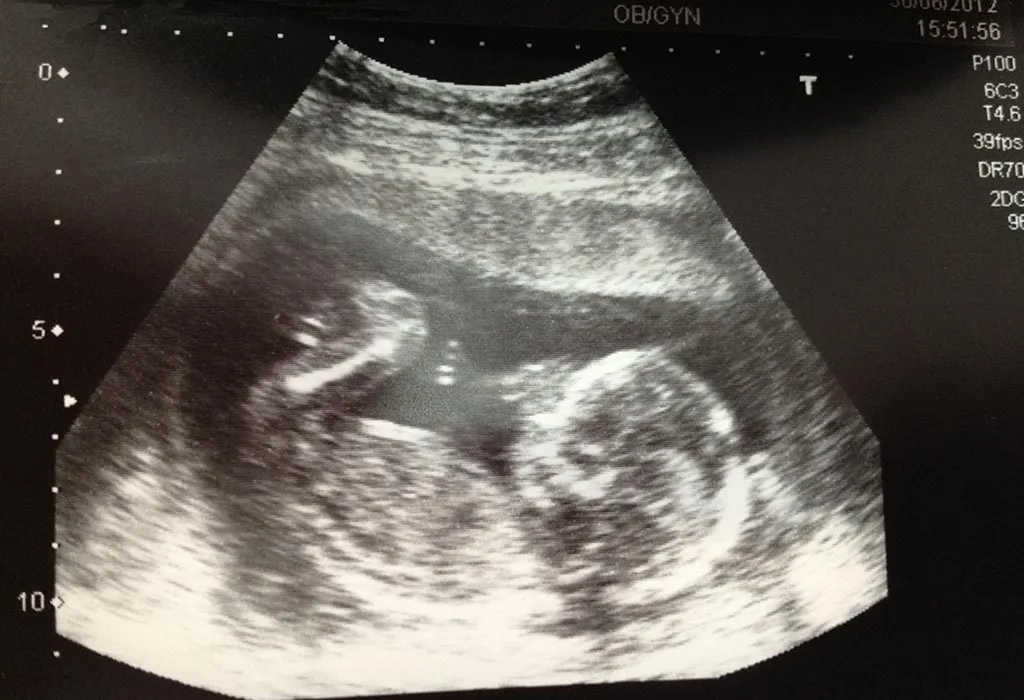

بارداری دوقلو در ماه چهارم

اگر مادری دوقلو باردار باشد، ماه چهارم، زمانی است که بسیاری از ویژگیهای متفاوت آن نسبت به بارداری تکجنینی نمایانتر میشود. اگرچه تا این مرحله، رشد جنینها تفاوت عمدهای با بارداریهای تکقلویی ندارد، اما علائم فیزیکی و نیازهای مراقبت سه ماه دوم بارداری متفاوتتر خواهد بود. تفاوتهای قابل توجه بارداری دوقلو با بارداری تکقلویی شامل موارد زیر میشود:

- افزایش وزن بیشتر مادر: مادرانی که دوقلو باردار هستند، معمولا در ماه چهارم، افزایش وزن بیشتری نسبت به بارداریهای تکقلویی دارند. این افزایش وزن بهدلیل رشد همزمان دو جنین، افزایش حجم مایع آمنیوتیک، بزرگتر بودن جفتها و افزایش بیشتر حجم خون در بدن مادر است.

- بزرگتر بودن شکم: شکم مادر در بارداری دوقلو در ماه چهارم، برجستهتر و بزرگتر از حد معمول بهنظر میرسد. رحم برای ایجاد فضای کافی جهت رشد دو جنین، سریعتر و بیشتر از حالت عادی گسترش مییابد.

ناگفته نماند که در ماه چهارم، رشد جنینهای دوقلو تقریبا مشابه رشد یک جنین تکقلو است. هر جنین سیستم گردش خون، اندامهای داخلی و ساختار بدنی در حال رشد خود را دارد. در صورتی که جنینها دو جفت و دو کیسه آمنیوتیک جداگانه داشته باشند که رایجترین حالت است، روند رشد آنها در این ماه تفاوت معناداری با جنین تکقلو ندارد.